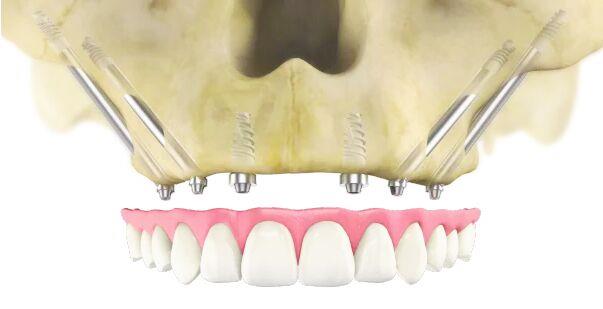

A special type of dental restoration is referred to as zygomatic implants, which are designed for patients with severe maxillary bone loss. These fixtures are surgically placed within the zygomatic bone, commonly known as the cheekbone, unlike conventional implants that are anchored in the jawbone. This alternative approach provides stability when traditional implantation isn’t possible because the bone structure doesn’t allow for conventional implants, and there’s no way to place them due to inadequate bone support. This allows for the creation of a stable foundation for the Dental prosthesis without any requirement of bone grafting. These implants are longer than traditional dental implants.

- Surgical placement – the surgery is performed under general anaesthesia or under local anesthesia. The type of Anesthesia depends on the patient’s and surgeon’s comfort ability. The surgeon makes small incision in the gum tissue and carefully dissect to reach the bone and places the zygomatic implants into the cheekbone. It is placed in a planned angulation and depth. In complicated cases a surgical guide is utilized to place the Implants.In many cases a temporary processes can be loaded immediately allowing you to leave the clinic with a full functional smile.

- No need for bone grafting– since the implants are placed in the cheekbones that are already very strong there is no need for a bone grafting procedures.